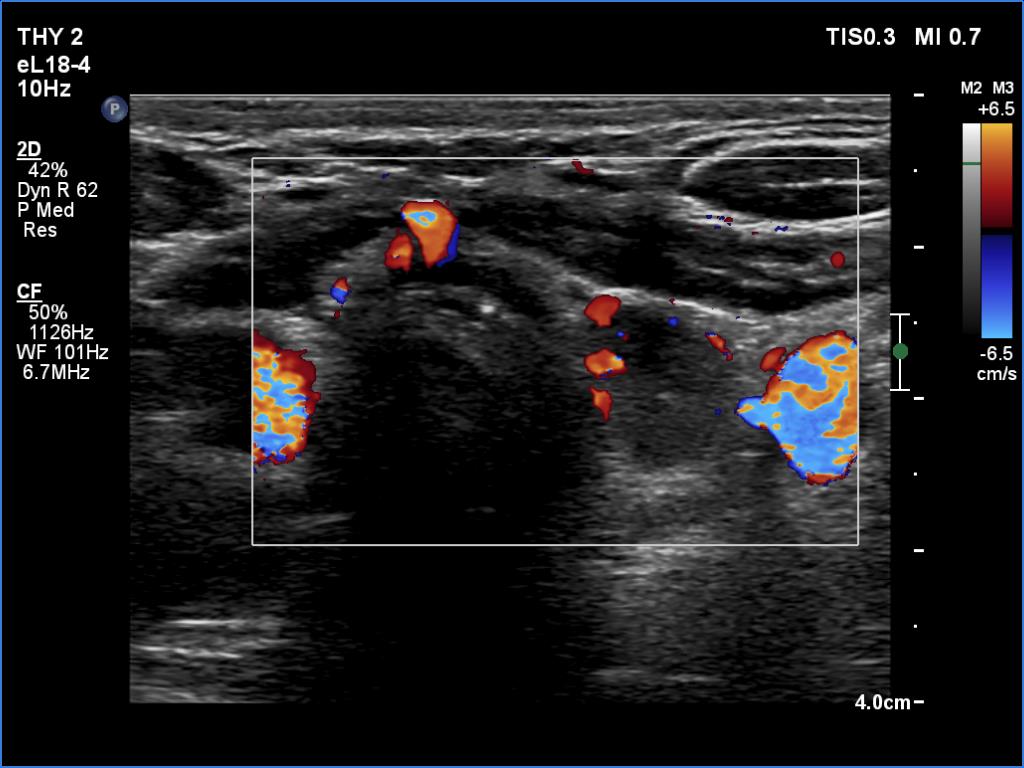

Ultrasonography revealed a hypoechogenic nodule in the ventromedial part of the left lobe. The nodule had irregular borders, contained microcalcifications and displayed perinodular and irregular intranodular blood flow.